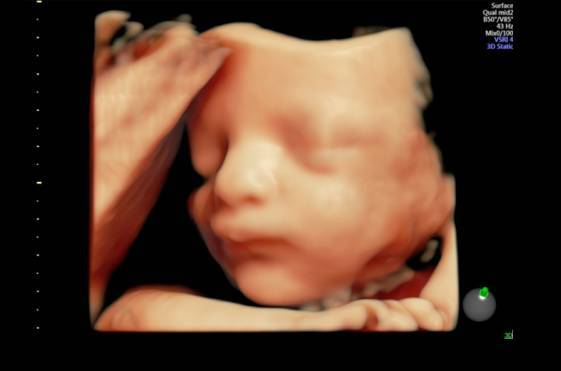

各孕期的胎儿系统筛查包括:1.胎儿孕11-13+6周NT筛查2.中孕期的三级/四级胎儿系统筛查3.3D/4D成像技术实时显示胎儿三维立体结构,实现胎儿表面重建,全面直观反映胎儿细...